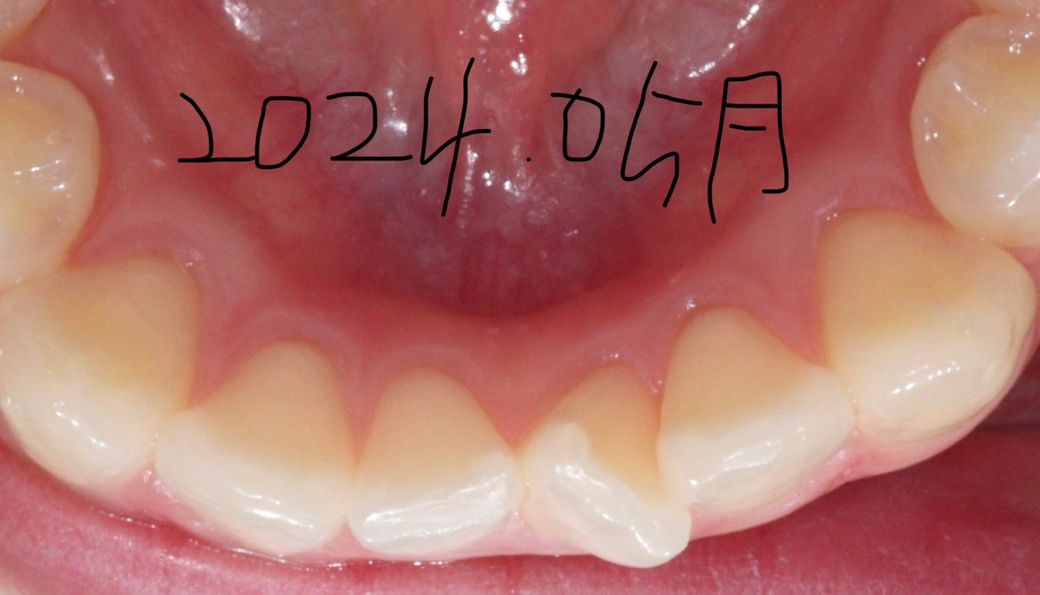

잇몸퇴축이 시작된거같아요 예방하고싶어요

교정한지 1년됐어요

잇몸퇴축 최대한 막으려면 어떻게해야하나요? ㅠㅠ

다른 잇몸퇴축이미지는 잇몸주변에 구내염처럼 흰 띠가 없는데, 저는 왜 흰 테두리가 있나요?

교정하기전부터 옅게 있었는데 아프지않아요

• 1번 째 사진

현재 보이는 정도로는 잇몸 퇴축이라고 할 수 없습니다. 교정 중에는 치아가 이동하므로 이동하면서 보이는 부분이 달라져 마치 퇴축된것처럼 보일 수도 있습니다. 하지만 지금과 같은 상태에서는 퇴축이 아닌 정상적인 상태로 보아야 하며 사진 상에서 병적 퇴축은 보이지 않습니다.

사진에 보이는 흰띠는 치아가 이동하면서 잇몸이 눌리면서 생기는 증상입니다. 교정을 하게 되면 잇몸이 조금씩 내려가는 경우가 있습니다. 교정으로 인해서 잇몸이 내려가는것을 막는 방법은 없습니다. 하지만 잇몸에 염증이 생기지 않도록 관리를 잘 한다면 잇몸퇴축이 더 일어나는것을 방지할수 있습니다.